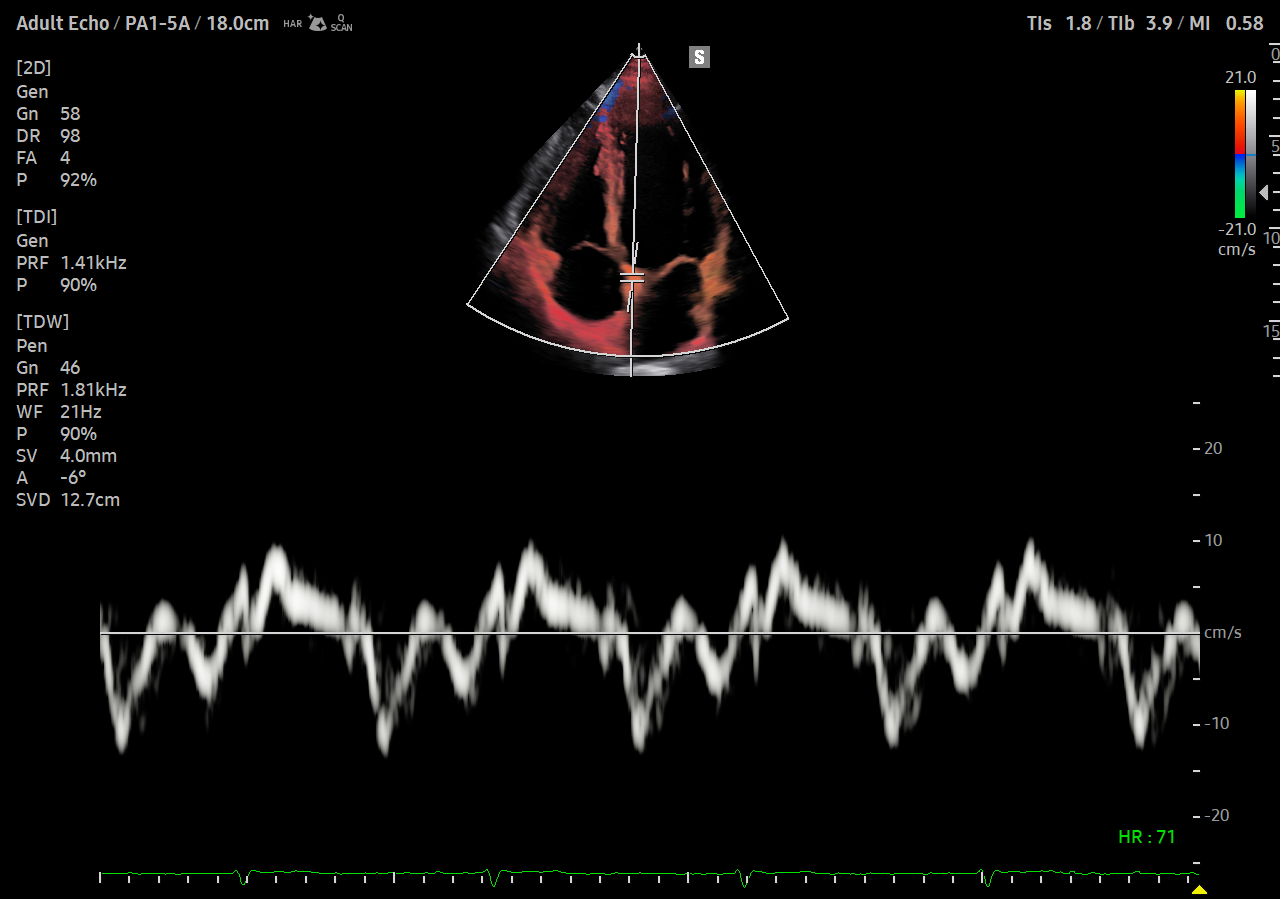

S-Flow , o tehnologie de imagistică Power Doppler direcțională, ajută și la detectarea vaselor de sânge periferice. Vă permite să faceți diagnostice precise atunci când examinarea fluxurilor sanguine este deosebit de complexă.

MV-Flow oferă imagini color avansate pentru vizualizarea structurilor microvasculare cu curgere lentă. Rata de cadre ridicată și filtrarea avansată permit MV-Flow să ofere o vizualizare detaliată a fluxului sanguin spațial.